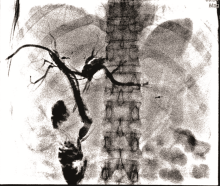

李勇:最终我们选择的治疗方案是胆道支架置入术联合碘125放射性粒子条治疗。如图3所示, 通过前期手术留置的PTCD引流管引入粒子条, 粒子条远端进入左肝管的一个主要分支、近端位于右肝管内; 从留置血管鞘应用双导丝引入一根超滑硬导丝, 沿硬导丝在左右肝管送入80 mm× 8 mm胆道支架一枚。利用支架膨胀张力使留置粒子条固定在胆道内, 然后引入导丝经已放置金属支架网眼进入胆总管、十二指肠, 建立轨道; 使用80 mm× 6 mm球囊扩张支架网眼后引入6F-Guide导管至胆总管中段, 沿导管送入一内装碘125的粒子条; 沿硬导丝在右肝管-胆总管送入80 mm× 8 mm胆道支架一枚。术后造影如图4所示。术前术后对比可以看到术后胆道情况明显好转。术后1个月复查CT(图5)示:与术前比, 肝内部分胆管轻度扩张, 以右叶为著, 左右肝管至胆总管下段内见支架植入, 支架内未见明显软组织影充填。

术后1个月复查总胆红素 37 μ mol/L, 结合胆红素19.9 μ mol/L(图6)。肝功能Child-Pugh评分为7分B级。